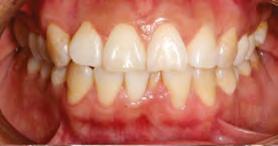

en paciente adulto tratado con extracciones de primeros molares permanentes. Reporte de caso

Dentista y Paciente 52 Sonriendo al futuro